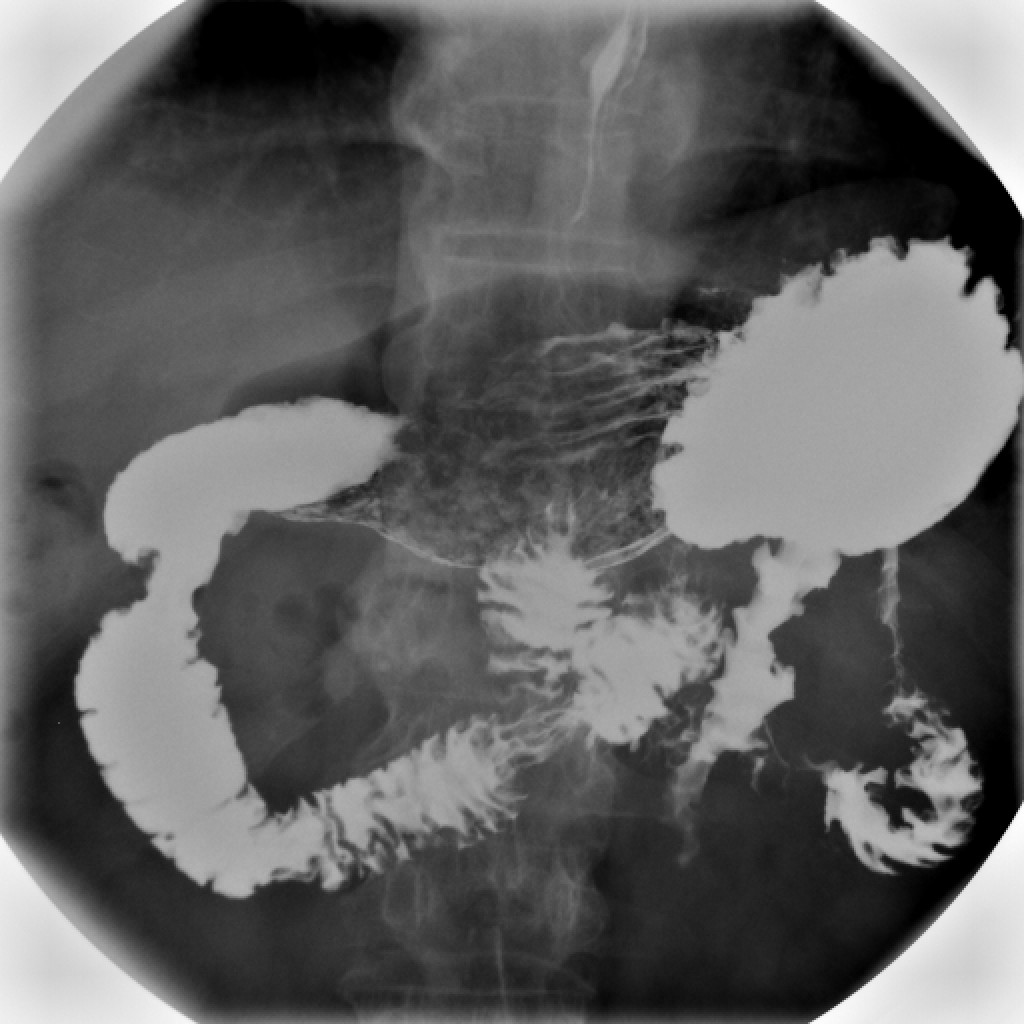

상부위장관조영술은 식도, 위, 십이지장을 검사하는 방법으로, 바륨을 사용하여 X-레이 촬영을 한다. 바륨 삼킴 엑스레이 검사(바륨 식도 조영술), 바륨 식사 검사, 바륨 추적 검사, 장액 주입술, 바륨 관장 검사 등이 있다. 상부위장관조영술은 식도 역류, 연하 곤란, 궤양, 종양 등 다양한 질환을 진단하는 데 사용되며, 소장 조영술은 소장의 형태와 병변을 확인하는 데 활용된다. 검사 결과는 방사선과 의사가 판독하며, 소장 질환, 연하곤란, 크론병, 위식도 역류 질환 등을 평가하는 데 도움을 준다. 검사 전에는 환자 동의가 필요하며, 방사선 노출, 변비, 알레르기 반응 등의 부작용이 발생할 수 있다. 황산바륨은 1910년 의료 조영제로 사용되기 시작했다.

바륨 엑스레이 검사는 검사 부위에 따라 다음과 같이 분류된다.[1]

- 바륨 삼킴 엑스레이 검사: 인두[3] 및 식도[1]를 검사한다.

- 바륨 식사 검사: 하부 식도, 위 및 십이지장을 검사한다.[1]

- 바륨 추적 검사: 소장을 검사한다.[1]

- 장액 주입술: 공장을 삽관하고 황산 바륨을 투여한 후 메틸셀룰로스 또는 공기를 투여하여 소장의 개별 고리를 표시하는 바륨 엑스레이 검사이다.[7]

- 바륨 관장 검사: 대장 및 직장을 검사하며, 하부 위장관 시리즈로 분류된다.[1]

상부 위장관 조영술은 식도, 위, 십이지장을 검사하는 방법이다.

바륨 X-선 검사는 위장관의 여러 부분을 검사하는 데 사용된다. 여기에는 바륨 삼킴 검사, 바륨 식사 검사, 바륨 추적 검사가 있다.[1] 바륨 삼킴 검사, 바륨 식사 검사 및 바륨 추적 검사는 함께 상부 위장관 시리즈(또는 검사)라고도 한다.[2] 상부 위장관 시리즈 검사에서는 황산 바륨을 물과 혼합하여 경구 투여한다.[1]

바륨 엑스레이 검사는 위장관의 외형과 기능을 연구하는 데 유용한 도구이다. 식도 역류, 연하 곤란, 식도열공 헤르니아, 협착, 게실, 유문 협착, 위염, 장염, 염전, 정맥류, 궤양, 종양, 위장관 운동 이상을 진단하고 추적 관찰하는 데 사용되며, 이물질을 감지하는 데에도 사용된다.[2][4] 컴퓨터 단층 촬영, 자기 공명 영상, 초음파 영상, 내시경 검사, 캡슐 내시경과 같은 더 현대적인 기술로 대체되고 있지만,[5] 바륨 조영 영상은 더 저렴하고, 더 널리 사용 가능하며,[6][7] 얕은 점막 병변을 평가하는 데 더 나은 해상도를 제공한다는 장점이 있어 여전히 널리 사용되고 있다.[5][8]